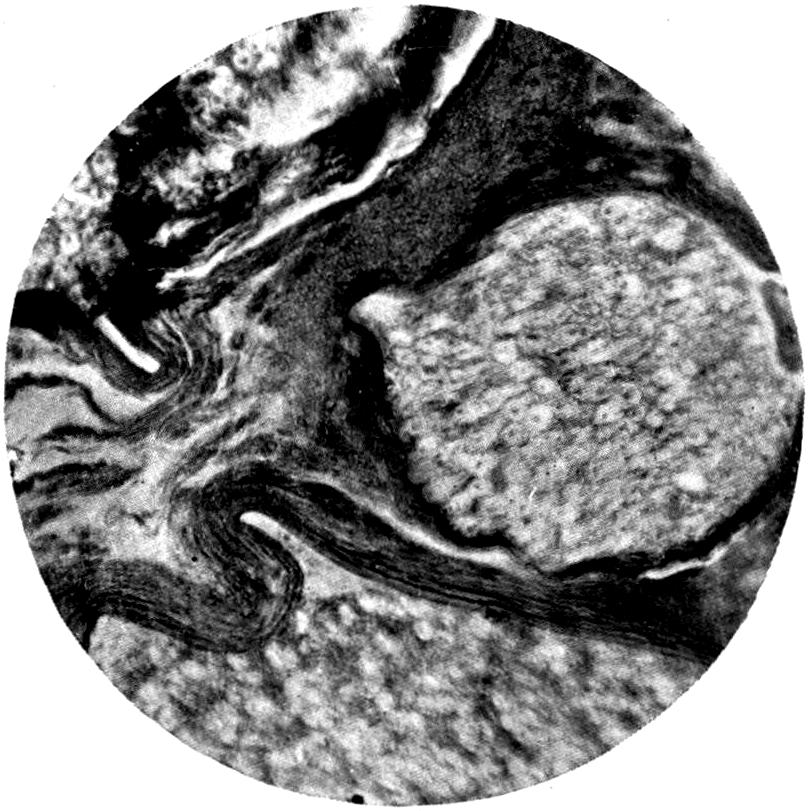

Plate I. 92